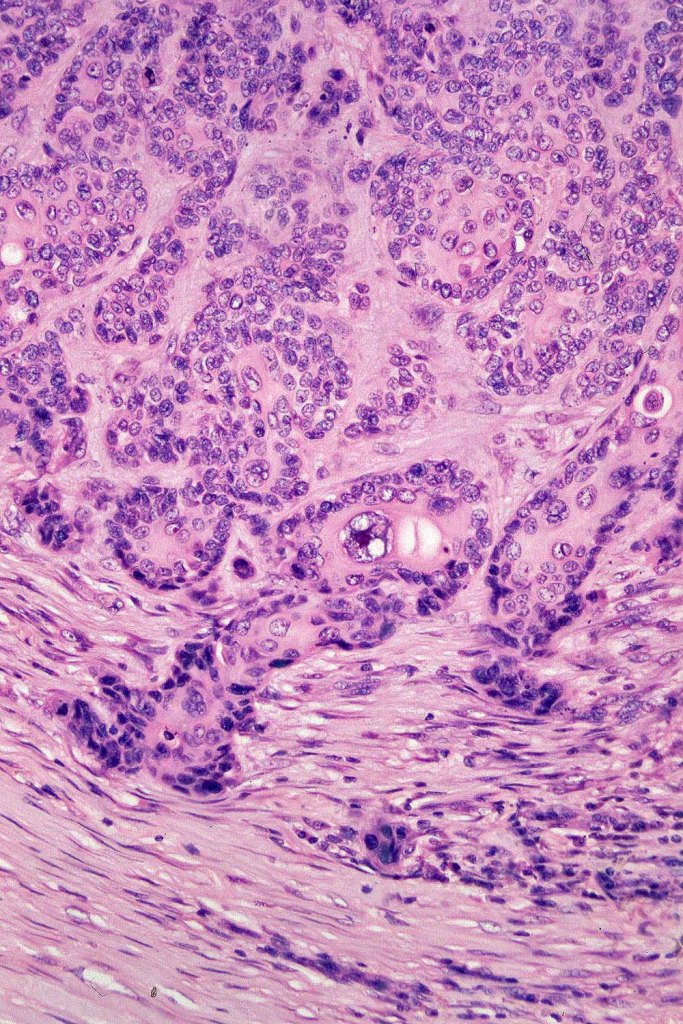

Histological features

•Continuity/origin from epidermis (arises from the acrosyringium, distinguishes this tumor from hidradenocarcinoma)

•Pushing or infiltrating deep margin

•Broad anastomosing epithelial trabeculae

•Mitoses often conspicuous and sometimes abnormal

•Variable necrosis (may be comedo-like)

•Ducal differentiation invariably present